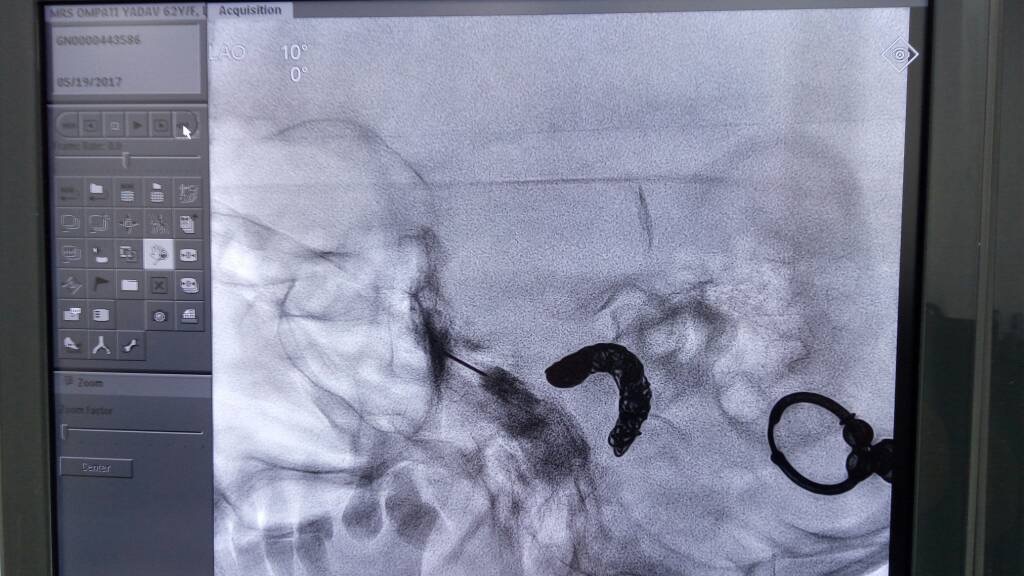

The patient is usually sedated, and using X-ray (fluoroscopy) guidance, a fine needle is placed near the SPG and anesthetic is injected. The patient will not feel numbness in the face. Pain relief may also not be immediate. If pain relief is good with local anesthetic but for a few days or weeks we do a radiofrequency ablation of SPG or neurolysis for long lasting pain relief.